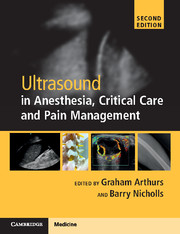

A transverse plane scan of the tissue volume beneath the planned site of skin incision should also be performed. The sonographer should inspect both the longitudinal and transverse scan images, looking for the presence of major blood vessels. In both planes, a 2D scan should be performed first. Blood vessels appear as a homogenous black area on a 2D scan. The operator can confirm the presence of a blood vessel by switching on the color Doppler ultrasound function (Figure 6.3*).